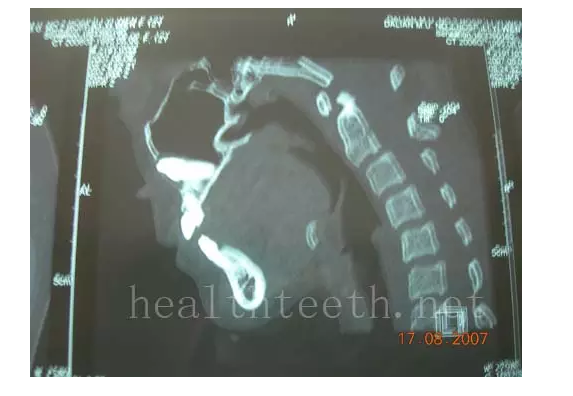

通過CT片確定埋伏牙齒具體的位置,顯示距離左側(cè)上頜竇很近,偏唇側(cè),這為手術(shù)定位提供了方便

手術(shù)中切斷、完整拔出,未損傷上頜竇